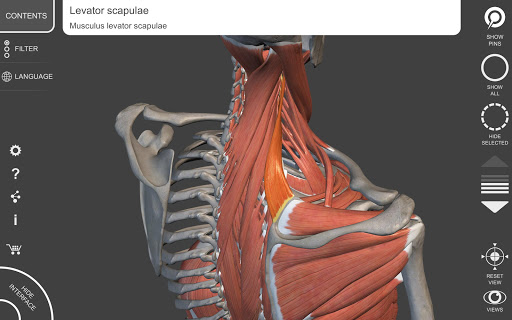

"Anatomy 3D Atlas" memungkinkan Anda mempelajari anatomi manusia dengan cara yang mudah dan interaktif.

Melalui antarmuka yang sederhana dan intuitif, Anda dapat mengamati setiap struktur anatomi dari sudut mana pun.

Model 3D anatomi sangat terperinci dan memiliki tekstur hingga resolusi 4k.

MODEL ANATOMI 3D

• Sistem muskuloskeletal

saraf • Sistem pernapasan • Sistem pencernaan • Sistem urogenital (pria dan wanita) • Sistem endokrin • Sistem limfatik • Sistem mata dan telinga FITUR • Antarmuka yang sederhana dan intuitif • Putar dan perbesar setiap model dalam ruang 3D • Opsi untuk menyembunyikan atau mengisolasi satu atau beberapa model yang dipilih • Filter untuk menyembunyikan atau menampilkan setiap sistem • Fungsi pencarian untuk menemukan setiap bagian anatomi dengan mudah • Fungsi penanda untuk menyimpan tampilan khusus • Rotasi cerdas yang menggerakkan pusat rotasi secara otomatis • Fungsi transparansi • Visualisasi otot melalui tingkat lapisan dari yang superfisial hingga yang terdalam • Dengan memilih model atau pin, istilah anatomi terkait akan muncul • Deskripsi otot: asal, • Tampilkan/ Sembunyikan antarmuka UI (sangat berguna dengan layar kecil) MULTIBAHASA • Istilah anatomi dan antarmuka pengguna tersedia dalam 11 bahasa: Latin, Inggris, Prancis, Jerman, Italia, Portugis, Turki, Rusia, Spanyol, Mandarin, Jepang, dan Korea • Istilah anatomi dapat ditampilkan dalam dua bahasa secara bersamaan PERSYARATAN SISTEM • Android 8.0 atau yang lebih baru, perangkat dengan RAM minimal 3GB Reversi